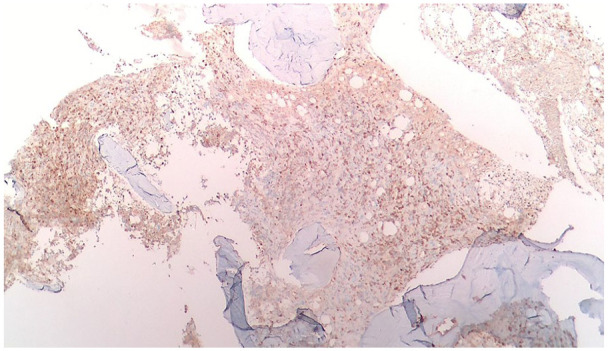

Abstract Image